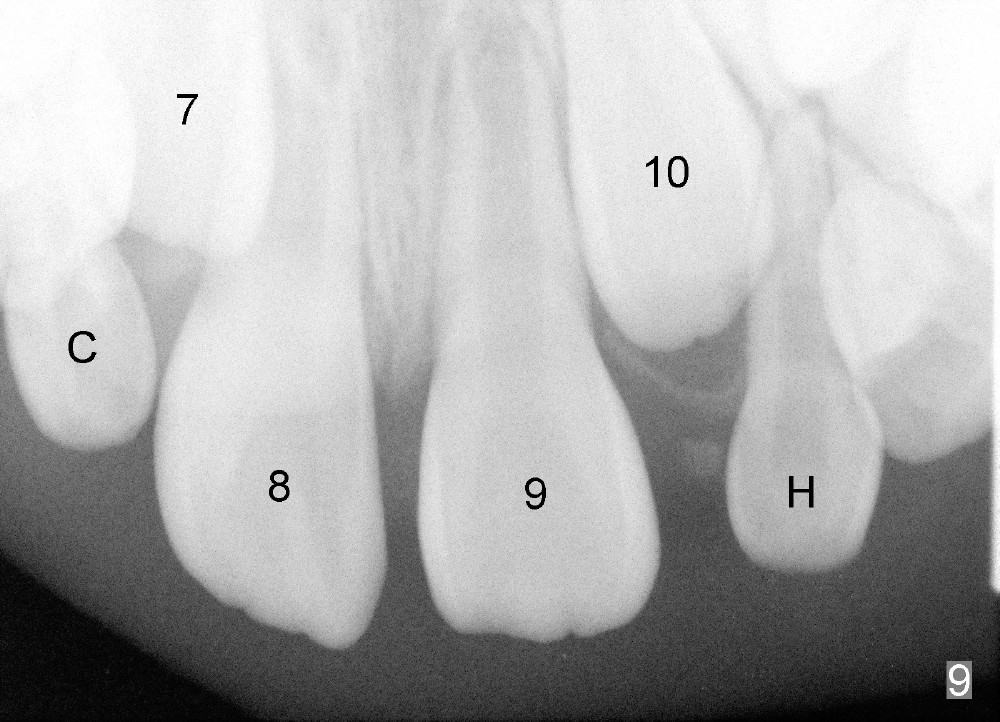

Now Devon is 7.5 years old. There is diastema between the centrals (Fig.9). #9 is in cross bite (Fig.10,11), while the lower incisors are crowded.

现在Devon七岁半,中切牙之间缝隙大(图九至十一:8,9),乳侧切牙已经脱落,但是没有足够间隙让恒侧切牙(图九:7, 10(C, H:乳尖牙))萌出,左上中切牙反合(图十:9),下切牙拥挤。